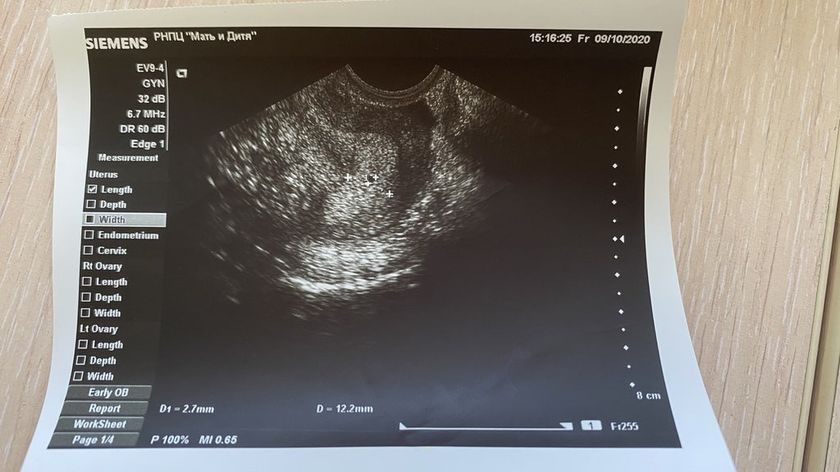

Во вторник сдала 137 мМЕ . Сегодня 37, завтра иду пересдавать анализ… была у врача, толком не объяснили, делали исходя с результата хгч что не развивающаяся беременность ? Может ли быть ошибкой лаборатории ?? Внутри себя надеюсь на ошибку, ничего не болит, выделений нет…